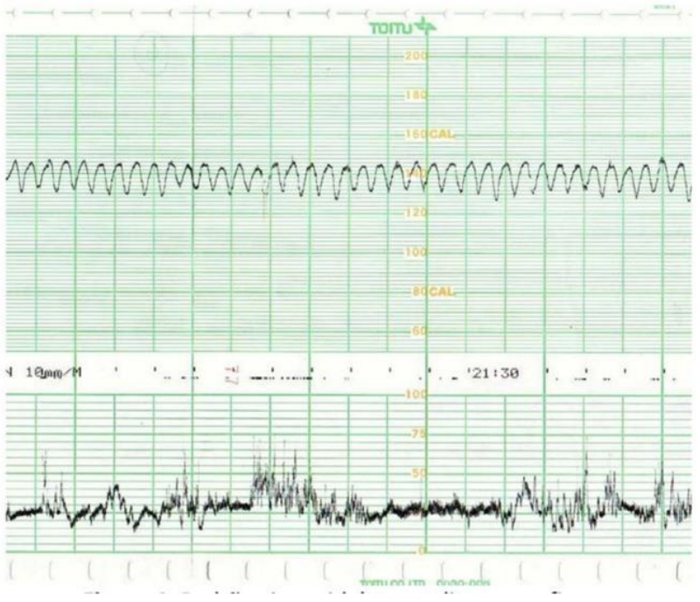

Sobre a cardiotocografia ante parto abaixo, pode-se afirmar:

Trata-se padrão sinusoidal, alto risco para óbito fetal.

Indica boa vitalidade fetal.